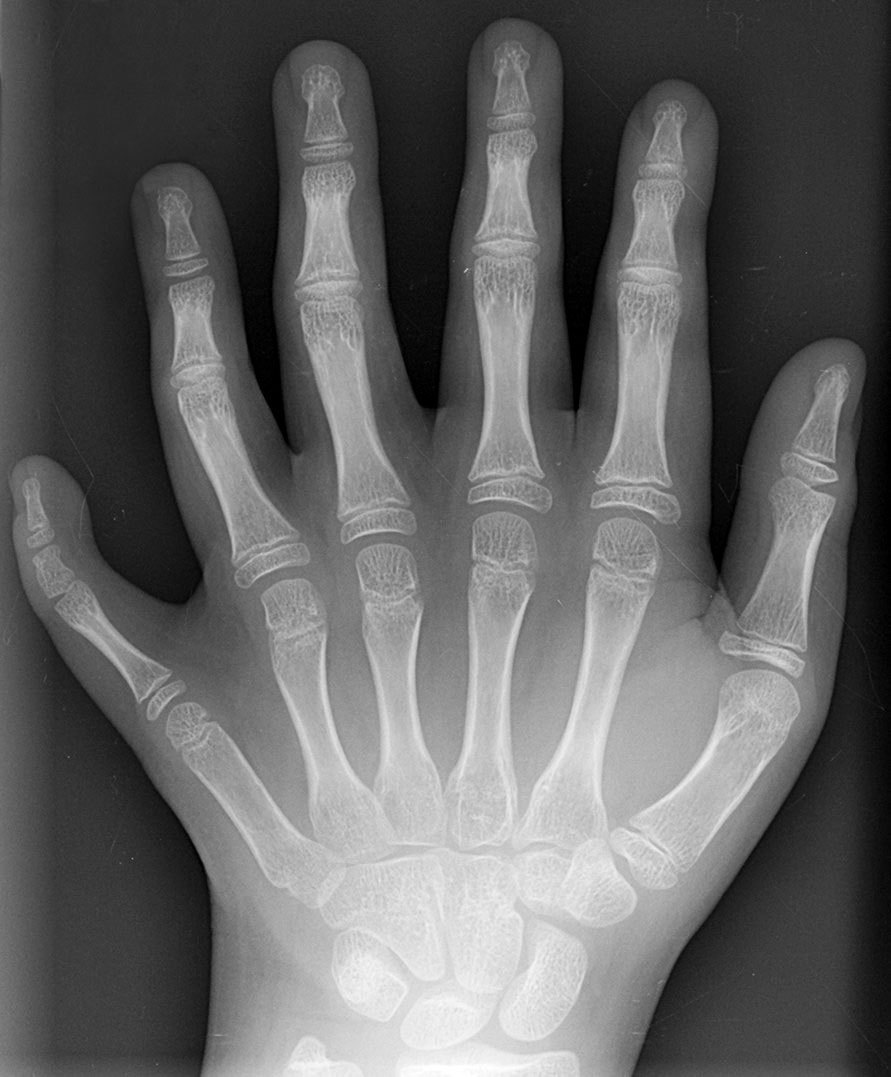

wiki-polydactyly.jpg

산부인과 관련해서는 구순열, 다지증 등 선천성 기형을 비정상으로 진단하는 기준입니다. 이런 기준점은 있고 없고라는 분명한 잣대가 있기 때문에 정상과 비정상에 대하여 구분하기가 그리 어렵지는 않습니다.